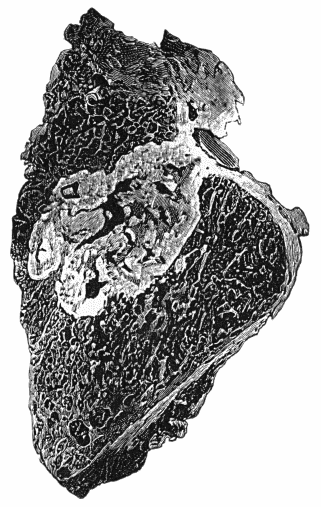

114.Section through Gouty Bursa 428